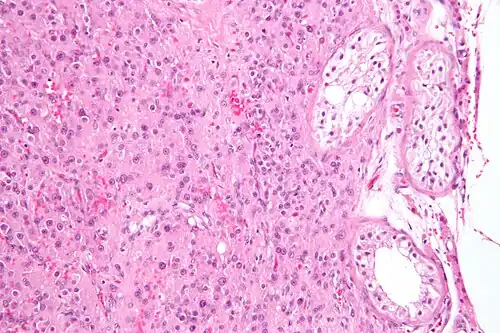

Micrograph of a Leydig cell tumour

Micrograph of a Leydig cell tumour